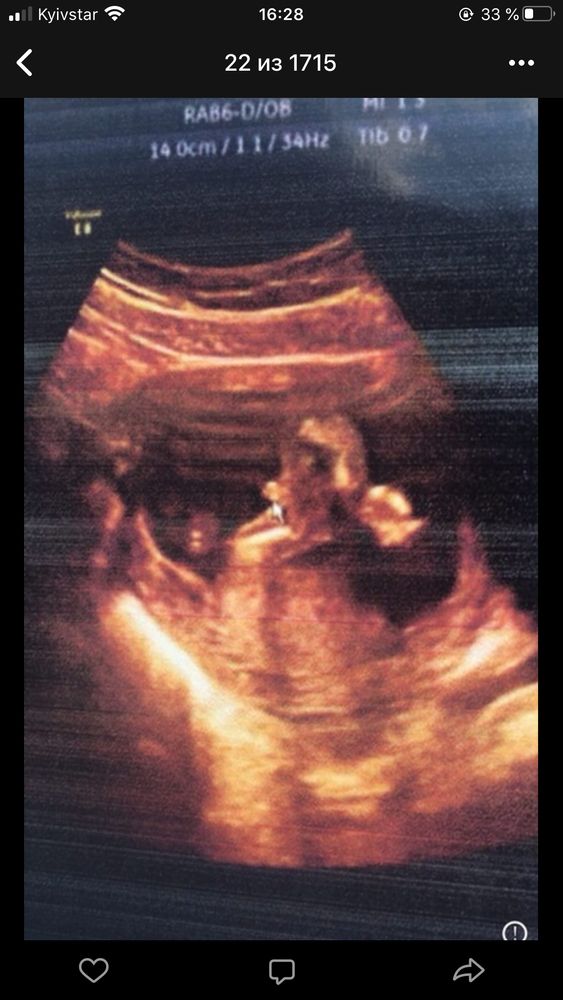

Сначала пообещали девочку, потом мальчика( фото прилагаю, но я думаю, что врач ошиблась), а сегодня малыш прятался и точно пол не сказали

Я, честно говоря, думала, что в Санкт-Петербурге такое вообще невозможно. Аппарат УЗИ хороший. Врач с опытом. Вот так и ошибаются с полом.

Да видно что аппарат хороший по снимку,я не так давно пост выкладывала там девушка выкладывала похожее фото и писала что по узи была девочка а родился мальчик вот так бывает..)